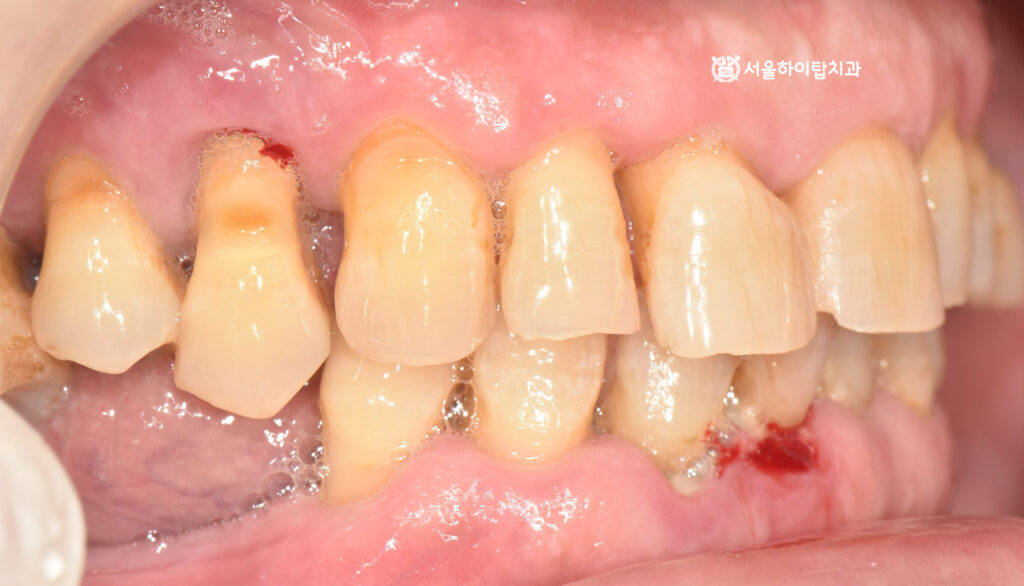

입을 다물었을 때 보는

측면, 정면 사진에서도

정출되어 치근이 보이는 모습과

출혈, 잇몸 부종, 전치부 마모 등

전형적인 심한 치주염의 양상을

보여주고 있습니다.

빠른 치료가 요구되는 상황입니다.